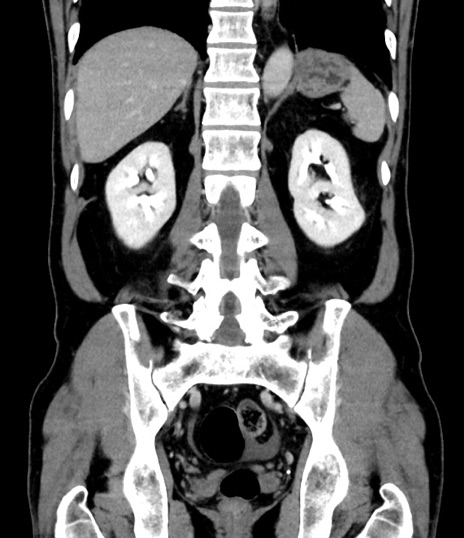

症例8(冠状断像)

【症例】 60歳代男性

【主訴】 黒色吐物

【現病歴】 4日前から嘔気自覚、2日前の朝食後にも嘔気あり、自分で手で嘔吐反射起こし嘔吐したところ血が混ざっていたため受診。

【既往歴】 5年前汎発性腹膜炎を伴う急性虫垂炎で手術、高血圧、前立腺肥大症、高脂血症

【身体所見】 腹部正中に手術癩痕あり 腹部平坦・軟圧痛なし膨満感あり

【データ】WBC 8400、CRP 4.54